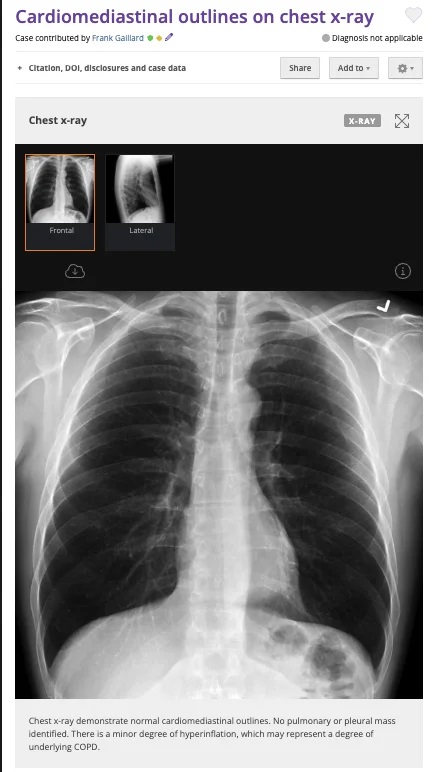

Orijinal görüntü 22 Ocak 2010’da bir radyoloji görüntüleri deposu olan “Radiopedia” üzerinden yayınlanmış.

• Fotoğraf, bir medikal arşiv sitesindeki göğüs röntgeni fotoğrafı manipüle edilerek oluşturuldu.